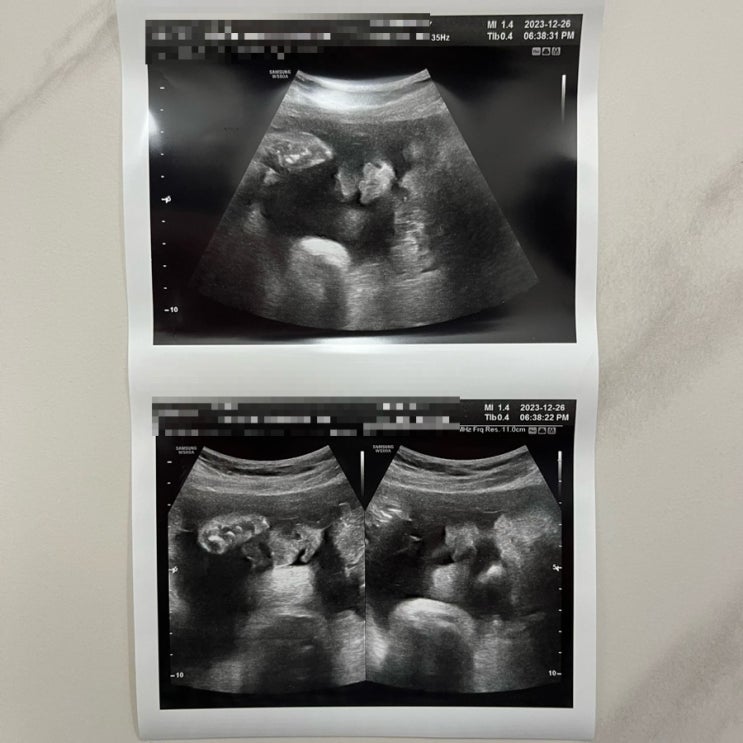

임신10개월 37주 일상_ 출산 전 마지막 검진

모찌는 쑥쑥자라 37주를 맞이함 ❤️ 이제까지 그래왔던것처럼, 얌전히 잘있다가 뿅 나와주길. 이번주차엔,...

임신9개월 35주 일상 _ 막달검사&선택제왕 수술날짜확정 / 새해&남편생일

어느덧 35주차에 접어든 모찌. 임신기간중 이벤트 1도없던거 실화? 넘 기특하다. 이번주차엔 막달검사가 기...